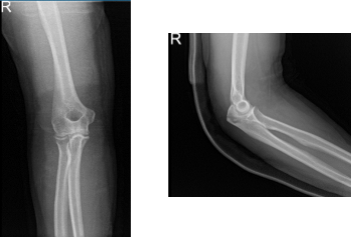

After the surgery, the patient was seen for a follow up check up and presented an X-ray result for right elbow that showed normal right elbow radiographs.

Right elbow x-ray